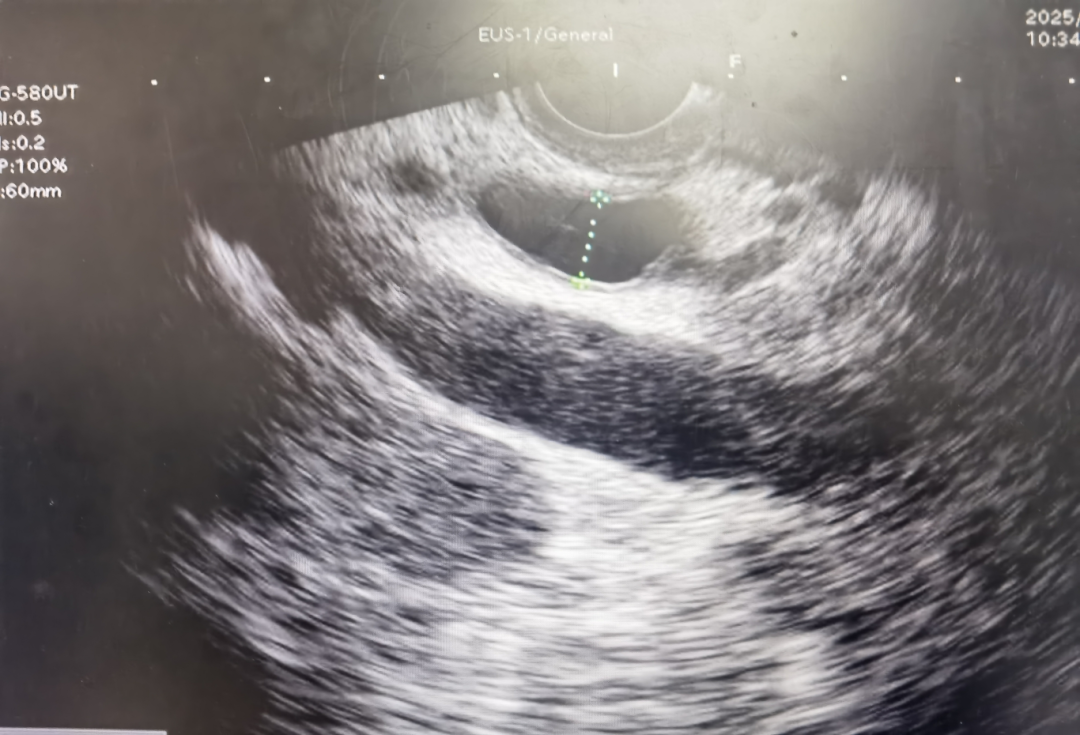

超声内镜(EUS)胆总管上段扩展并胆管炎

超声内镜(EUS)便是破解这一难题的关键技术!超声内镜(EUS)像一名“医学侦探”精准锁定胆总管内的隐藏结石,并通过ERCP微创取石,迅速缓解危机!胆总管结石是引发腹痛、黄疸的常见病因,但有些结石“藏得深”,常规检查难以发现。